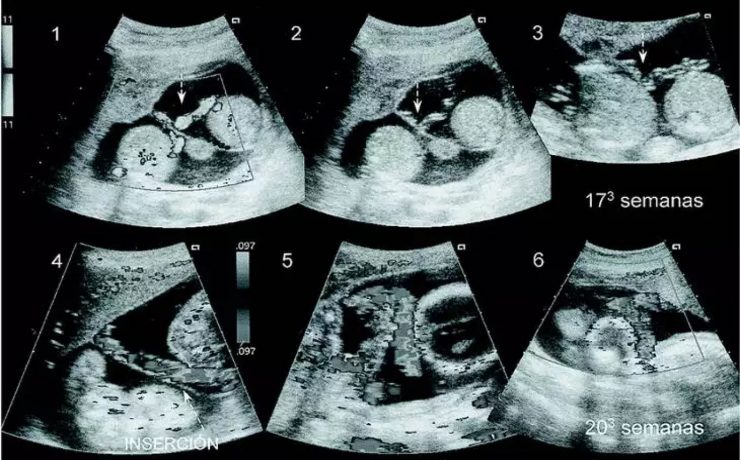

Quiste hidatídico primario de bazo

La hidatidosis es una enfermedad causada por Equinococus granulosus y que afecta principalmente a zonas endémicas donde existe disminución de la higiene, lugares con corrales o animales con problemas intestinales, alimentos donde se consumen vísceras crudos, en lugares urbanos se ha visto este tipo de patología donde abundan los perros